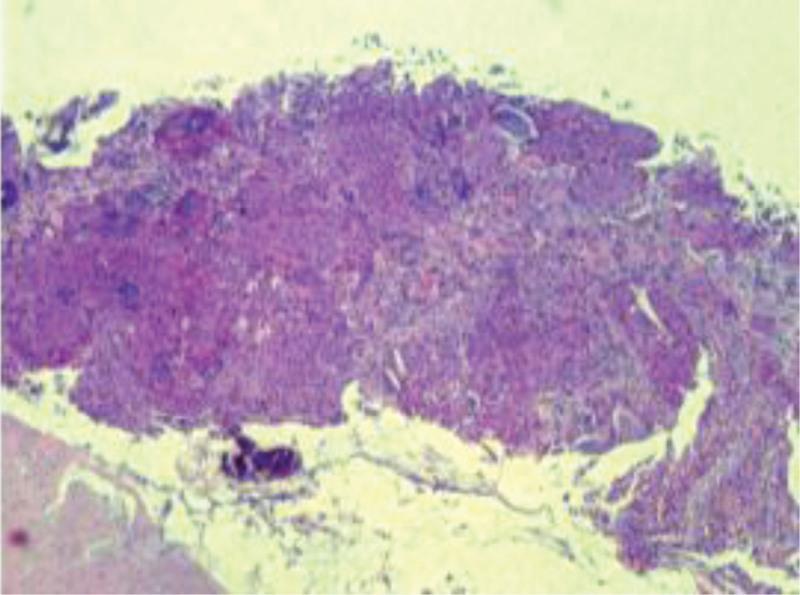

One patient was diagnosed with PMEC combined with ALK mutation.

PMEC combined with ALK mutation is an extremely rare primary lung cancer, and the diagnosis is mainly based on pathology, histology and immunohistochemistry. The application of molecularly targeted drugs to patients with mutations can significantly improve the prognosis of patients with PMEC, which is expected to be a new breakthrough in the treatment of PMEC.